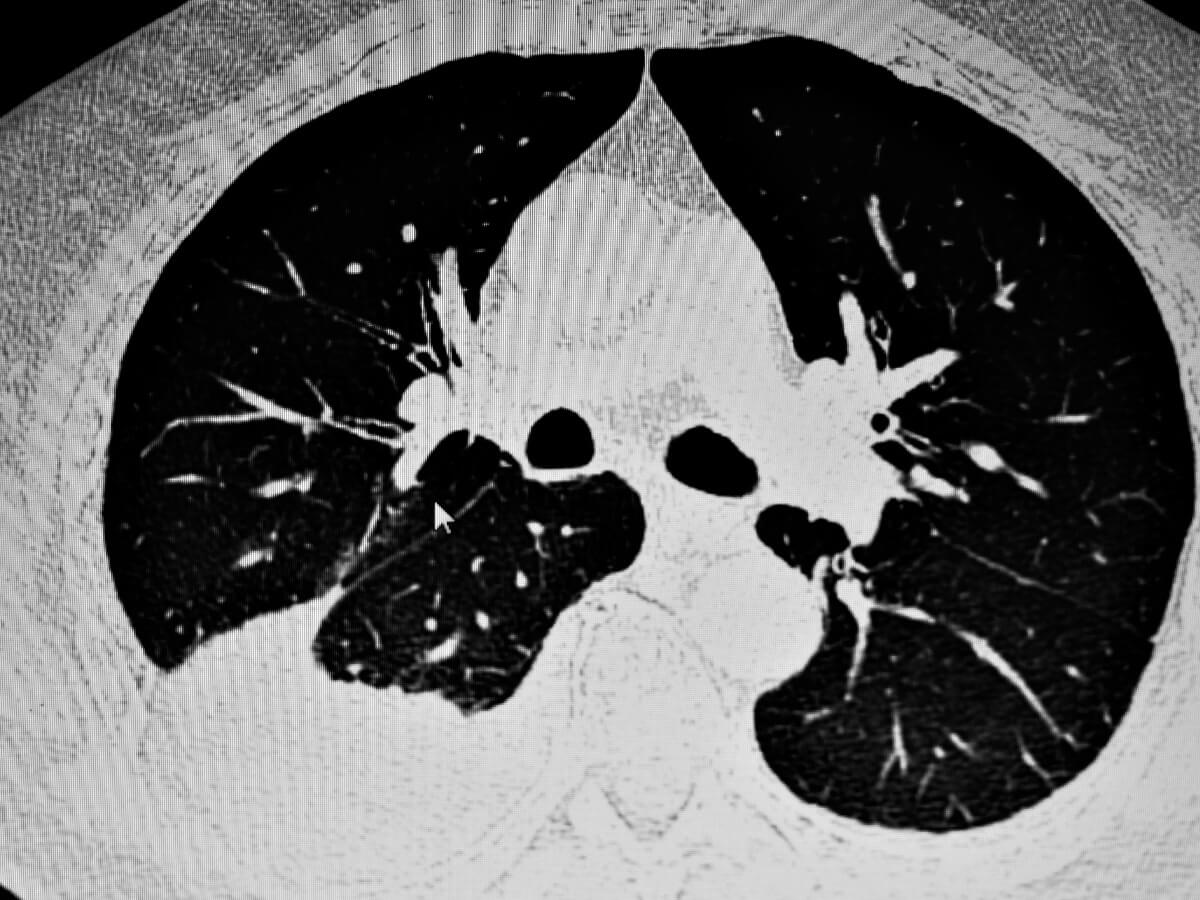

Once a respiratory problem is suspected, x-rays are usually used to directly observe the animal’s medical condition. Ultrasounds can be helpful, especially when the amount of fluid accumulated in the pleural cavity is very low.